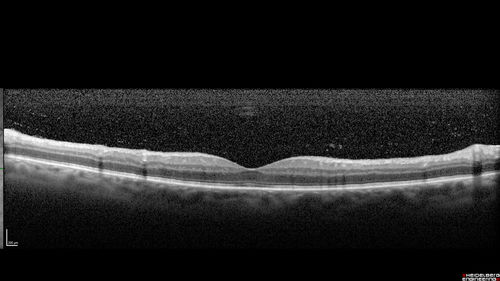

Chronic Endophthalmitis and Cystoid Macular Edema

VA 20/50 - Culture negative. Cleared with intravitreal antibiotics and decadron